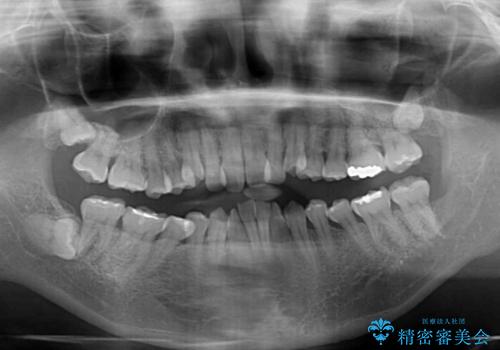

飛び出した上顎前歯と上下のデコボコ 片顎の抜歯によるワイヤー矯正

- 上下前歯のデコボコと、上顎の八重歯を気にして来院された患者様です。

下顎に対して上顎が前方にあり、第一大臼歯による咬合状態は上顎前突であったため、上顎のみ左右の第一小臼歯を抜歯し、ワイヤー装置にて矯正治療を行うこととしました。

舌の突出癖が強く、治療途中で上下前歯が乖離した開咬となってしまいました。

舌のトレーニングで開咬は改善できますが、なかなかトレーニングが進まず、治療期間は想定よりも長期化してしまいました。